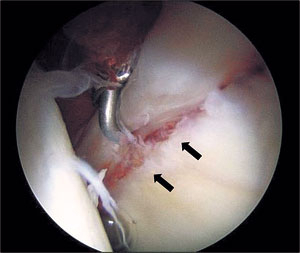

육상선수인 김철민(가명'16) 군은 2년간 오른쪽 고관절 통증에 시달려 왔다. 수차례 검사를 받았지만 특이점을 찾지 못했다. 종합병원을 찾아 검사한 결과 '대퇴비구 충돌증후군'(대퇴골두를 감싸는 비구가 지나치게 튀어나왔거나 비구의 변형 탓에 비구와 대퇴골두가 부딪치면서 통증을 느끼는 질환. 고관절 충돌증후군)으로 진단됐다. 이런 경우 비구 끝에서 대퇴골을 감싸는 부드러운 부위인 '비구순'이 손상된 경우가 많기 때문에 관절경 수술로 충돌 부위를 잘라냈고, 통증이 사라졌다.

버스 기사인 조형주(가명'50) 씨도 석 달간 왼쪽 고관절 통증에 시달리다 병원을 찾았다. 다른 병원에서 MRI, CT 등 여러 검사를 받았지만 이상을 찾지 못했다. 통증 때문에 일도 못할 지경이었다. 종합병원을 찾았지만 추가 검사를 거부했다. 통증으로 볼 때 비구순 파열 가능성이 높아 결국 관절경 수술을 받았고, 손상 부위를 잘라낸 뒤 통증에서 벗어났다.

관절경 수술은 약 1㎝ 이하의 작은 구멍 2, 3개를 뚫은 뒤 초소형 카메라와 레이저 수술기구가 들어 있는 가는 관을 관절 내부로 집어넣어 질환 부위를 진단하고 치료하는 방법이다. 무릎이나 어깨 관절에서 많이 시술되고 있다. 고관절은 워낙 체내에 깊숙이 위치하고 주위 조직이 다른 관절에 비해 두껍고 튼튼하기 때문에 관절경을 통한 접근이 어려워 널리 시행되지 못했다.

1980년대 이후 수술방법 및 기구의 발전과 함께 고관절 통증에 대한 많은 연구가 이뤄지면서 점차 고관절에도 관절경 수술을 하는 경우가 늘고 있다. 환부를 절개하지 않고 약 1㎝ 이하의 작은 구멍을 통해 초소형 카메라를 집어넣은 뒤 모니터로 관절 내부를 볼 수 있기 때문에 MRI, CT로도 파악되지 않던 질환을 눈으로 직접 확인해 정확한 진단을 할 수 있다. 아울러 수술을 통한 치료도 동시에 이뤄지기 때문에 통증이 적고 조기에 보행 및 퇴원이 가능하며 후유증이나 합병증도 최소화할 수 있다.

특히 비구순 파열은 고관절 통증의 주요 원인이 될 수 있다. 비구순 파열은 단순 방사선 사진으로는 진단이 어렵다. 관절경은 가장 정확히 진단하는 동시에 수술까지 가능한 장점이 있다. 또 고관절 내에 퇴행성 변화나 외상 때문에 골절편(유리체)이 생기는 경우가 많은데 관절경을 통해 절개하지 않고 제거할 수 있다. 초기 골관절염 환자의 경우, 관절경을 통해 연골의 어느 부위가 얼마나 닳았는지 정확히 알 수 있다. 특수 시술을 하면 일시적으로 관절염의 진행을 지연시키는 효과도 있다.